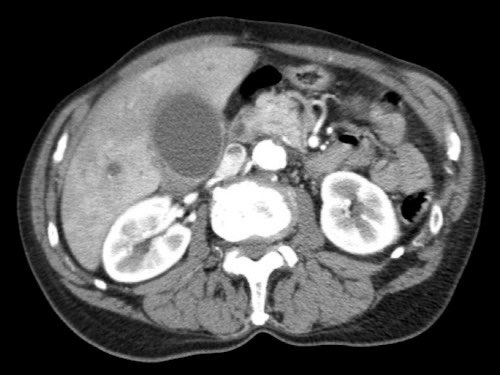

Việc sử dụng tái tạo đa mặt phẳng (multiplanar reformation) giúp cải thiện hiệu quả chẩn đoán tổng thể của CT, như được minh họa trong trường hợp này.

Tái tạo mặt phẳng coronal cho thấy một khối u nhỏ ở đầu tụy (đầu mũi tên) gây tắc nghẽn ống mật chủ.

Có vẻ chỉ có tiếp xúc hạn chế với tĩnh mạch cửa (mũi tên).

Tiếp tục xem các hình ảnh tiếp theo.

Tái tạo đa mặt phẳng vuông góc với tĩnh mạch cửa cho thấy mức độ tiếp xúc với tĩnh mạch cửa rộng hơn, từ 90 đến 180 độ (mũi tên).

Khi không có bất thường bờ viền, trường hợp này được phân loại là có thể cắt bỏ giới hạn (borderline resectable) theo tiêu chí DPCG, nhưng có thể cắt bỏ (resectable) theo tiêu chí NCCN.

Phẫu thuật cắt bỏ không kèm tái tạo tĩnh mạch cho kết quả R1, tức là có xâm lấn vi thể của khối u tại diện cắt.